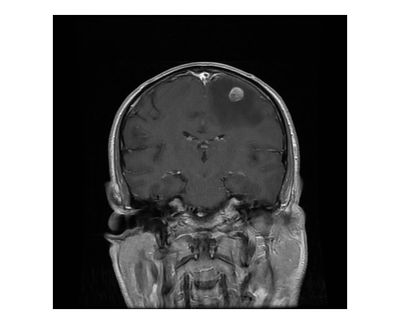

Dr. Morreale treats disorders of the brain including brain tumors, aneurysms, infections and trauma. Dr. Morreale also performs functional neurosurgery also for conditions including Parkinson's Disease, essential tremor and other movement disorders.